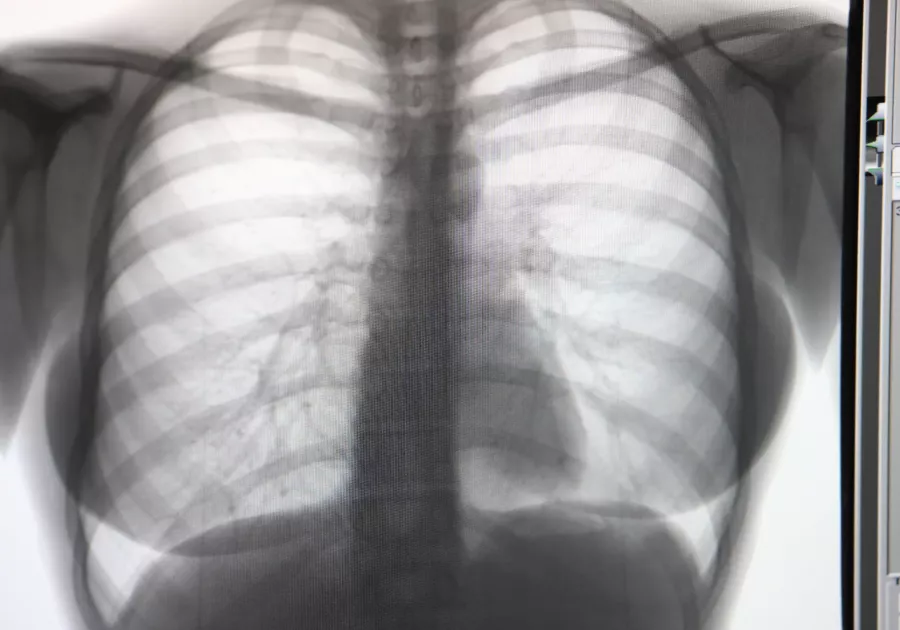

Хорошо зарекомендовал себя проект по службе сопровождения пациентов с подозрением на злокачественное новообразование. Его основная задача – сокращение сроков с момента подозрения до постановки диагноза или же его опровержения.

– Здесь важно взаимодействие с онкологическим диспансером, у нас оно налажено через информационную систему, – объясняет Дмитрий Попов. – То есть все обследования и подозрения на диагноз сразу появляются в медицинской системе на уровне края и мы понимаем, как можно оказать помощь.

Срок, который ставится в этом случае – не более десяти рабочих дней. В течение этого времени должны быть осуществлены все необходимые исследования и проведена консультация в онкодиспансере. Если возникает проблема на каком-либо этапе: в проведении исследования, например, то задача перенаправляется в другое медучреждение, где есть возможность ее решить быстрее.